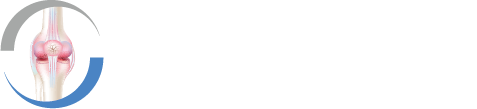

Eine präzise Diagnostik ist entscheidend, um die Art und Schwere einer Meniskusverletzung zuverlässig festzustellen. Als Kniespezialist kombiniere ich klinische Erfahrung mit modernster Bildgebung – für eine sichere und individuelle Therapieentscheidung.

- MRT (Magnetresonanztomographie):

Das wichtigste Verfahren zur Diagnose eines Meniskusrisses. Die MRT liefert präzise Bilder von Meniskus, Bändern, Knorpel und Weichteilen. - Röntgen:

Je früher ein Meniskusriss erkannt wird, desto besser sind die Heilungschancen – ob durch konservative Therapie oder einen minimalinvasiven Eingriff.